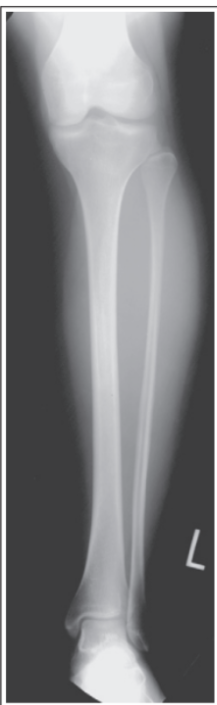

Tibia superimposed with less than ¼ of fibula head

Internal rotation

Tibia superimposes more than ½ of the fibular head

Internal rotation/ under-rotated

Tibia superimposes less than ½ of the fibular head

External rotation/ under-rotated

Less than ½ of the fibula head is superimposing with tibia

More than ½ of the fibula head is superimposing with tibia

External rotation